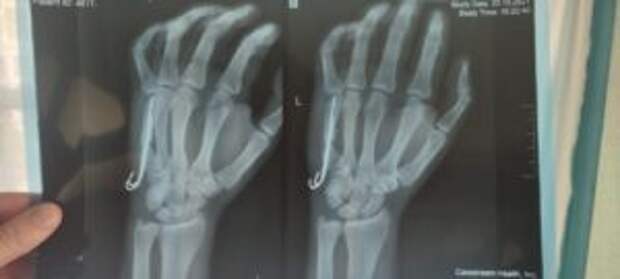

Diagnóstico: Fractura por arma de fuego del quinto metacarpiano con desplazamiento. Se ha formado una articulación falsa, se requiere fusión ósea.